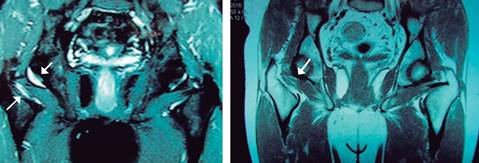

Hombre de 65 años, jugador de tenis en fines de semana, inició con dolor intenso posterior a envío de servicio y correr hacia la red, el dolor se refirió en región glútea, trocánter mayor y región inguinal derecha con irradiación a cara posterior de tercio superior de muslo. Permaneció en reposo relativo por ocho días con antiinflamatorio, sin mejoría, referido por su médico a rehabilitación sin diagnóstico definitivo. A la exploración inicial en rehabilitación se encontró: paciente con marcha claudicante a expensas de miembro pélvico derecho, con ayuda de bastón a mano contralateral, con dolor a la palpación de trocánter mayor derecho y dolor inguinal intenso a la rotación interna de cadera. El examen clínico muscular a nivel de cadera derecha no fue preciso por dolor intenso a la movilización pasiva y activa: reflejos osteotendinosos normales. Con diagnóstico presuncional de fractura por estrés de cuello de fémur derecho se solicitó resonancia magnética, la cual mostró ruptura de músculo cuadrado crural derecho (Figura 1). Se inició tratamiento con esteroide a dosis única, tramadol 10 mg cada 12 horas y programa de terapia física a base de ultrasonido a dosis de 1.6 watts/cm2 aplicado del trocánter mayor al isquion derecho cada tercer día por 12 sesiones, en la octava sesión se agregaron movimientos de rotación externa e interna de cadera derecha a tolerancia, así como ergómetro y reeducación de la marcha en banda. El paciente fue dado de alta a las 20 sesiones de terapia física con arcos de movilidad de cadera completos, fuerza muscular en 5/5 y asintomático.

El músculo cuadrado crural1 se encuentra en la parte posterior de la cadera, tiene relaciones con los nervios ciáticos mayor y menor (de ahí sus manifestaciones de dolor a la región glútea), los vasos isquiáticos que lo cruzan verticalmente; por delante está en relación con la cápsula articular (origen de las manifestaciones de dolor a la región inguinal). Su acción es de rotador externo de la cadera por lo que al efectuar rotación interna pasiva o activa origina dolor por estiramiento. Su lesión es poco frecuente, con incidencia desconocida, siendo sus manifestaciones clínicas dolor en región glútea y/o región inguinal. De acuerdo con el reporte de O’Brien y colaboradores,5 esta lesión se presenta principalmente en el género femenino con relación 6:1 con edades comprendidas entre 18 y 43 años, siendo la mayoría rupturas aisladas grado II en la unión músculo-tendinosa, causadas durante la práctica de deportes con raqueta (semejante al paciente presentado). El mecanismo de lesión se da al tratar de controlar la rotación interna de cadera inmediatamente el envío del servicio, generando una contracción excéntrica de los rotadores externos de cadera (entre ellos el cuadrado crural) que ocasiona la ruptura de sus fibras. Debido a lo infrecuente de la lesión, por lo regular no se diagnostica de primera intención, siendo necesario el estudio de imagen para llegar al diagnóstico de certeza. En 80% de los casos clínicos registrados de lesión de cuadrado crural los hallazgos de RMN3 indican presencia de edema o hemorragia de la unión músculo-tendinosa del cuadrado crural entre el trocánter mayor y la tuberosidad isquiática. El cuadro puede manifestarse posterior a la osteotomía de cadera y a la colocación de prótesis de la misma. Tanto la ruptura del cuadrado crural como su pinzamiento deben ser parte del amplio diagnóstico diferencial de los problemas de cadera.